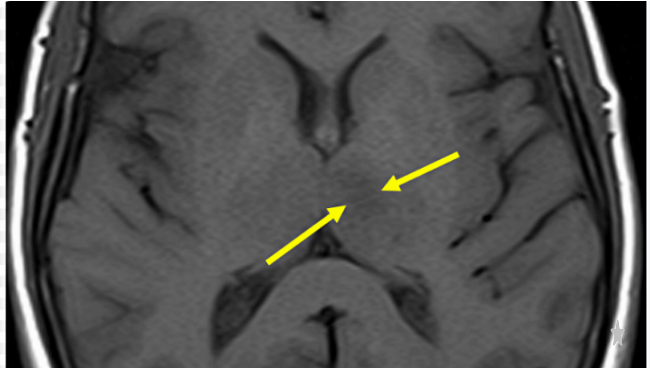

특히 주의해야 할 상태가 바로 일과성 허혈성 발작입니다.

이는 뇌경색 전조증상과 동일한 증상이 나타났다가 24시간

이내에 사라지는 현상을 말합니다. 증상이 일시적으로

호전되었다고 해서 안심하는 경우가 많지만 이는 곧 큰

뇌졸중이 닥칠 것이라는 강력한 경고입니다.

실제로 해당 증상을 겪은 환자의 상당수가 며칠 내에 본격적인

뇌경색으로 이행되기 때문에 반드시 병밀 검사를 받아야 합니다.